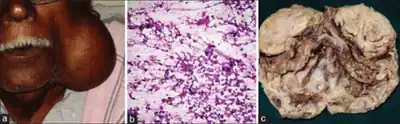

.jpg) Histopathology of Warthin tumor in the parotid gland. H&E stain. (Fig 1)

Histopathology of Warthin tumor in the parotid gland. H&E stain. (Fig 1) -

.jpg) Histopathology of Warthin tumor in the parotid gland. Another view of Fig 1

Histopathology of Warthin tumor in the parotid gland. Another view of Fig 1 -

.jpg) Histopathology of Warthin tumor in the parotid gland. Higher magnification of a Fig 1

Histopathology of Warthin tumor in the parotid gland. Higher magnification of a Fig 1 -